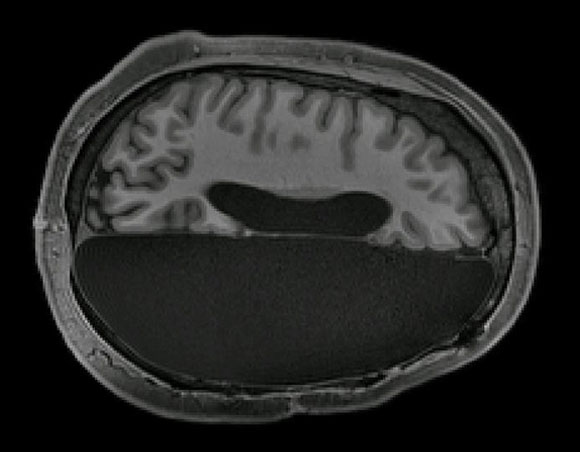

טיפול קיצוני. סריקת מוח של אדם שעבר הֶמִיסְפֶרְקְטוֹמְיָה, כריתת מחצית המוח | Caltech Brain Imaging Center

במחקר השתתפו שישה בוגרים שאחד מחצאי המוח שלהם הוסר בילדותם המוקדמת, לפני גיל 11. לחולים נעשו סריקות של דימות תהודה מגנטית (MRI) שהושוו לסריקות של שישה אנשים בריאים. כמו כן נכללו במחקר סריקות של 1,482 מוחות נוספים של אנשים בריאים שנעשו במקור לצרכים אחרים. ההשוואה העלתה שדפוס הפעילות של המוח במצב מנוחה אצל החולים דומה להפליא לזה של אנשים בריאים.